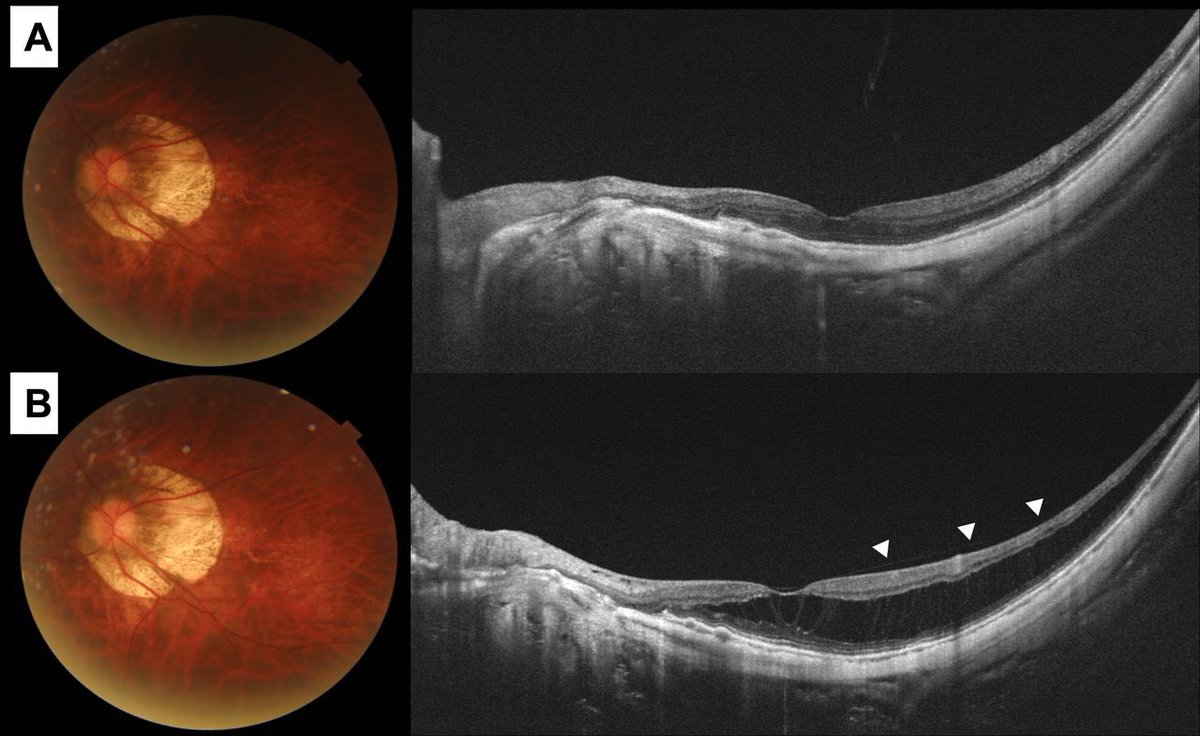

يعتبر قصر النظر عالي اذا تجاوز -٦ او الحجم الطولي للعين ٢٦.٥مم او اكثر ، ويعتبر مرضي اذا صاحبه تغيّرات مرضيّة في الشبكية

احد المضاعفات الخطيرة المحتملة هي نمو اوعية دموية من مشيمة العين الى الشبكية، وتسبب ضعف الرؤية وتموجها

وتعتبر حالة طارئة تستدعي العلاج الفوري عن طريق حقن العين بعلاج والمتابعة، استجابة الاوعية الدموية للحقن في حالات قصر النظر العالي تعتبر ممتازة وسريعة في غالب الحالات